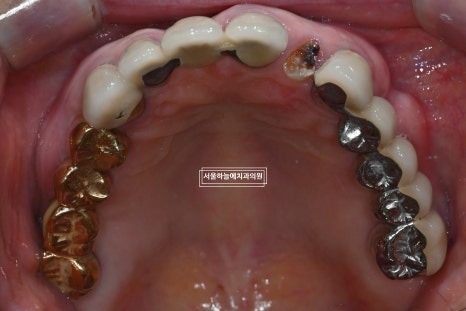

처음 내원 당시 엑스레이와 구강 상태를 보면

앞니는 파절되어 있었고

아래 어금니가 없는 기간이 길어

위 치아와 잇몸이 맞닿을 정도로 공간이 부족,

아래 앞니 역시 심하게 마모된 상태였습니다.

앞니 부위 임플란트 1개 식립

아래 양쪽 어금니 부위 임플란트 각 2개 식립

마모가 심한 아래 앞니는

크라운 치료를 통해 교합 높이 조정

이후 아래 어금니 임플란트 보철물 장착